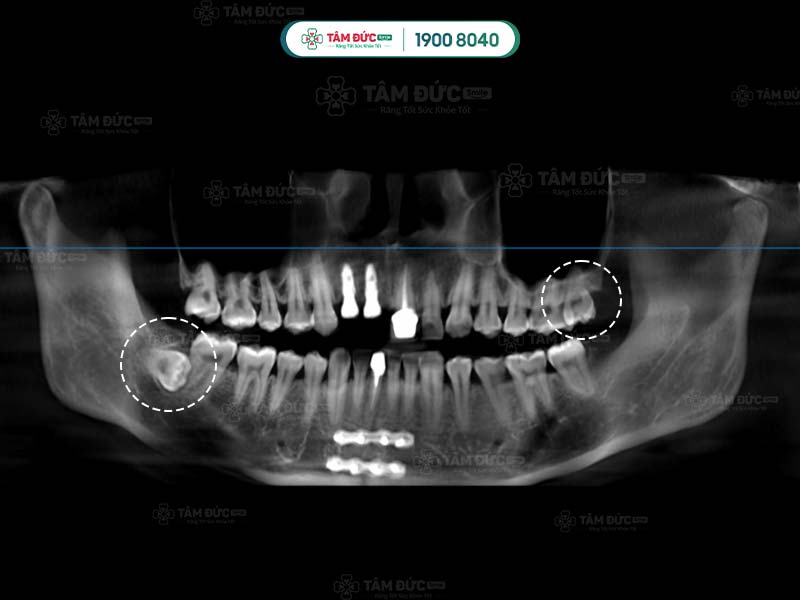

Răng khôn qua phim chụp X-Quang

Hình dạng của chân răng khôn hay còn gọi là gốc răng khôn ở mỗi người có sự khác biệt. Răng khôn có hình dáng khác với những chiếc răng còn lại, chúng hầu như có từ 2, 3 thậm chí là 4 gốc răng. Các chân này thường hợp nhất với nhau tạo thành chân lớn. Tuy nhiên, một số khác lại cuộn tròn hoặc xòe ra các hướng khác nhau.

Một số trường hợp đặc biệt, răng khôn có thể có nhiều hơn 4 chân răng. Chính vì thế, việc biết được răng khôn có mấy chân là điều cần thiết giúp bác sĩ lựa chọn giải pháp nhổ răng khôn an toàn nhất.

Chân của răng khôn có thể xòe nhiều hướng với nhiều hình thái khác nhau. Ngoài ra, việc răng khôn mọc ngầm cũng tiềm ẩn nhiều nguy hiểm. Nếu để thời gian lâu dài, chân răng khôn mọc ngầm hoặc lệch có thể ảnh hưởng đến các dây thần kinh xung quanh.

Sau khi nhận kết quả chụp phim, bác sĩ tiến hành đánh giá tình trạng và độ khó của phẫu thuật. Tiếp đến, Quý khách sẽ được tiêm thuốc gây tê tại chỗ. Với trường hợp răng khôn dễ nhổ: bác sĩ tiến hành rạch trên nướu, làm sạch vùng phẫu thuật để tiếp cận và nhổ bỏ răng khôn. Trường hợp khó hơn: răng khôn có nhiều chân thì cuộc phẫu thuật có thể kéo dài. Lúc này bác sĩ sẽ rạch và cắt từng chân của răng khôn để đảm bảo an toàn.